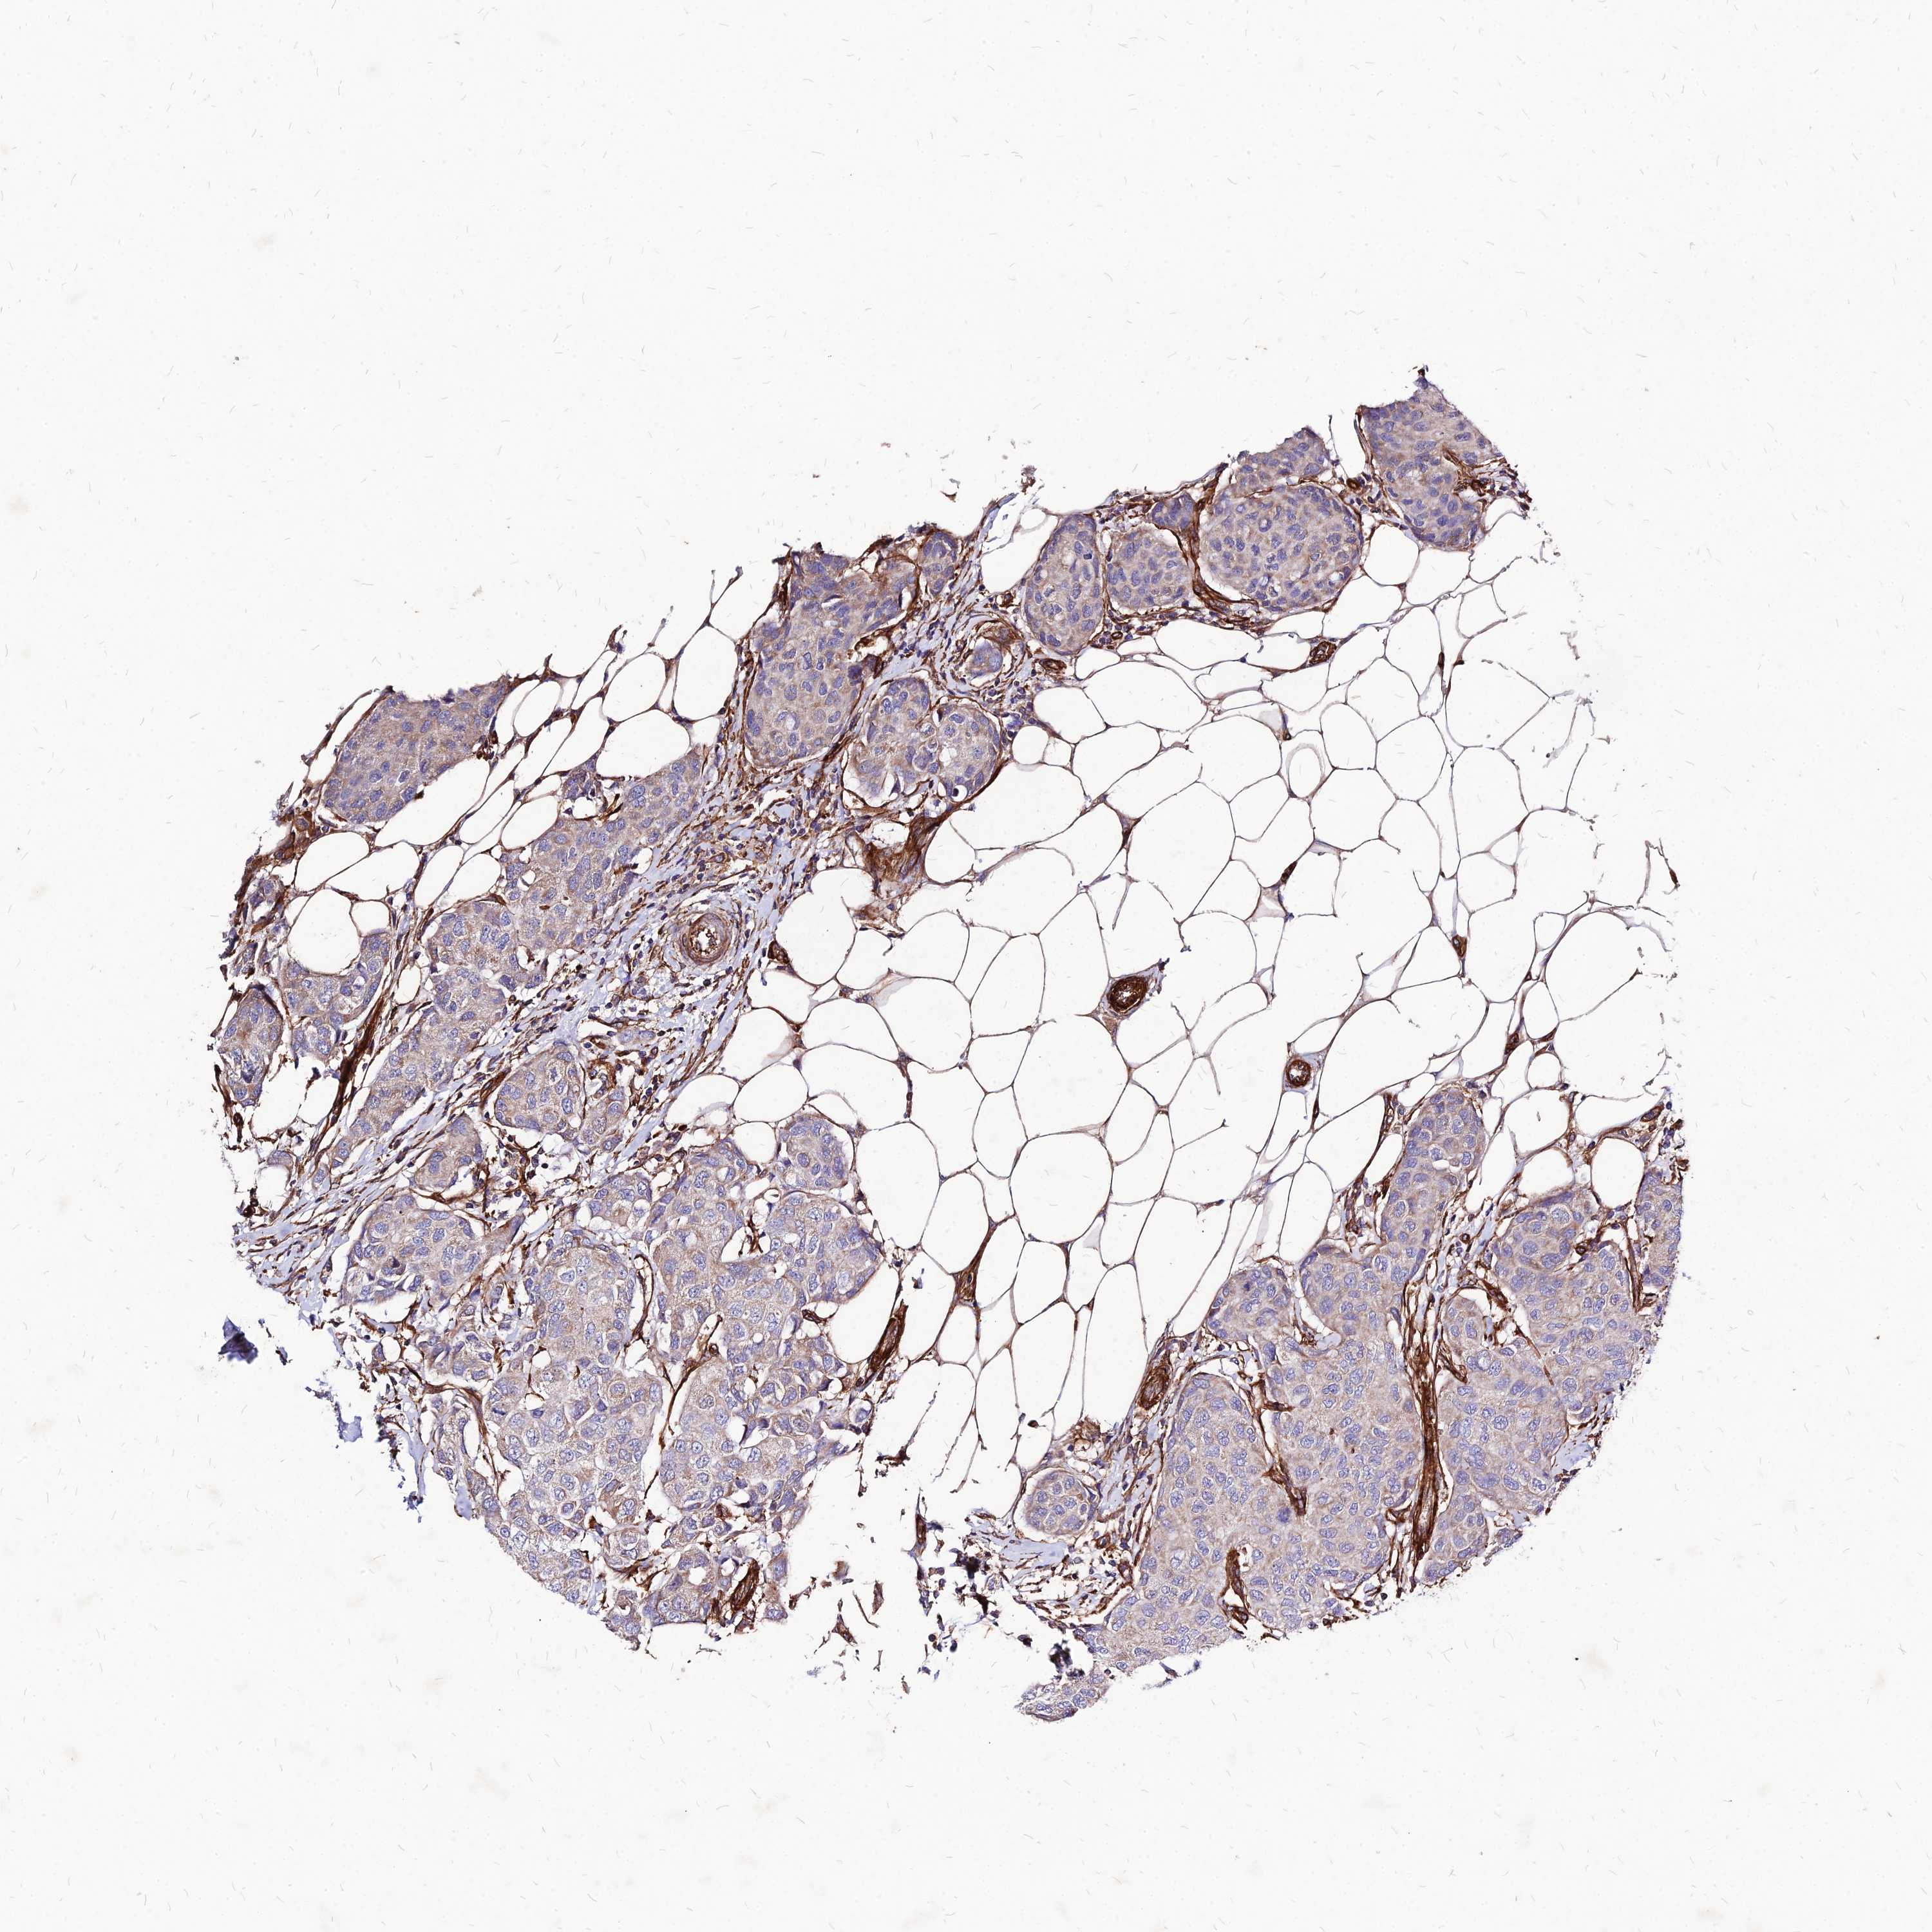

BRCA TCGA BRCA VALIDATION PROTEIN EXPRESSION